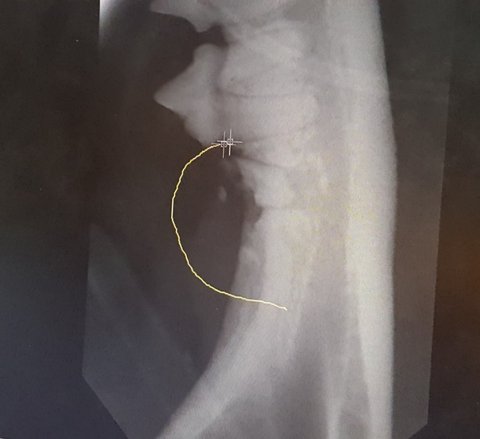

발치한 이빨입니다.

총 네 개라더군요.

점박이의 발치된 부분의 엑스레이 사진입니다.

엑스레이 사진의 아랫부분의 이빨이 뻥 뚫려서 공동이 생겨 있습니다.

이 이빨도 발치를 했습니다.

의사 선생님이 그러시더군요.

고양이의 입안에 문제가 생긴 것은 모두 구내염이라고 일반적으로 말하지만 엄밀하게 말하면 진짜 구내염은

후 구내염이라고 하는 것만 의미를 한답니다.

후 구내염은 전체 발치를 하고서도 지속적인 관리를 요하는 그야말로 어려운 질병이랍니다.

하지만 점박이의 경우는 후 구내염은 아니랍니다.